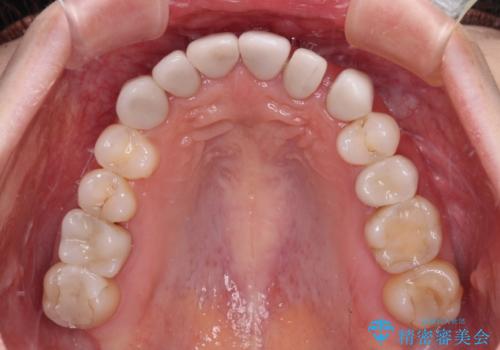

- 全体的なデコボコと、奥歯の欠損を放置した結果倒れ込んだ奥歯などを気にして来院された患者様です。

ワイヤー矯正の方が理想的な仕上がりとできる状態でしたが、上顎前歯にクラウンが装着されているため、インビザラインにて矯正治療を行うこととしました。

インビザラインのみで対応できないときにはワイヤー矯正を併用することとし、矯正治療後にはオールセラミッククラウンによる補綴治療を行うこととしました。

矯正治療自体はインビザラインで満足のいく仕上がりとなりました。

前歯は根管治療が必要となり、元々舌側に入り込んでいた左上2番目の歯は歯周外科処置により歯肉ラインを整えることとしました。

欠損部位は傾斜歯軸を起き上がらせることができたため、オールセラミッククブリッジにて補綴治療を行いました。

全顎的に満足のいく仕上がりとなりました。